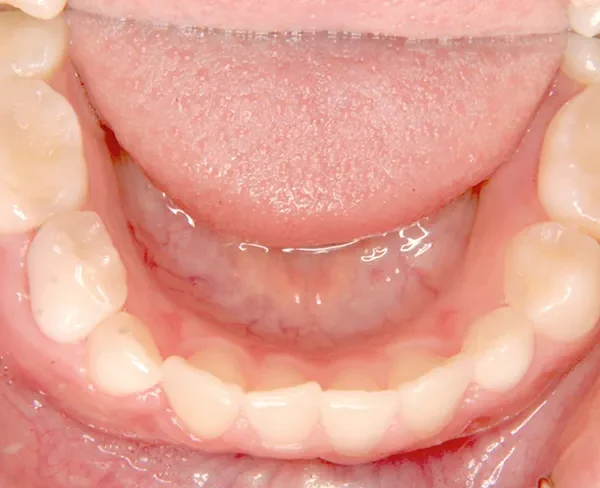

上の前歯が下の前歯より後ろに入って、受け口になっています。

下の歯は永久歯の生えるスペースがないので、オリジナル矯正装置で受け口を治して、永久歯の生えるスペースを作りました。

状態 永久歯が生える隙間がない(叢生)

受け口(下顎前突/反対咬合)